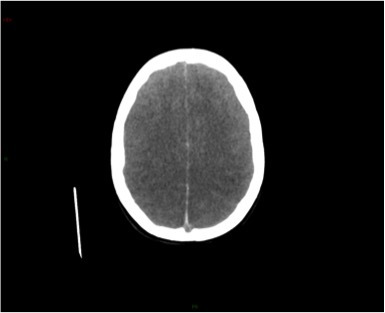

Ci-dessous des coupes axiales Diffusion et Flair de l’IRM cérébrale. La séquence T2* ne présente pas d’anomalie.

Question 5 : Après analyse de cette IRM, votre diagnostic est :

Hypersignaux diffusion à la limite de la visibilité en Flair.

Hypersignaux diffusion, sans anomalie franche de signal Flair ni perte de substance éliminant ce diagnostic

L’IRM montre de multiples AVC ischémiques aigus (i. e.  6 heures), corticaux et sous-corticaux, dans des territoires artériels différents.